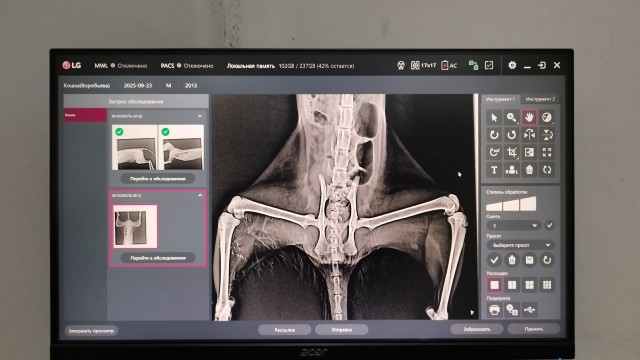

Теперь у Елены ещё + 2 инвалида, она и Маркиз, чем-то их ситуации схожи, у обоих по рентгену нет никаких замечаний, кости целы, но оба не могут ходить, задние лапки не работают!(((

Чтобы до конца понять дальнейшие перспективы по Маркизу, нужно везти его на КТ, а это ценник достаточно дорогой, само КТ стоит 12000, + к нему необходимы свежие анализы крови + УЗИ диагностика сердца, т.к. оно делается под наркозом.